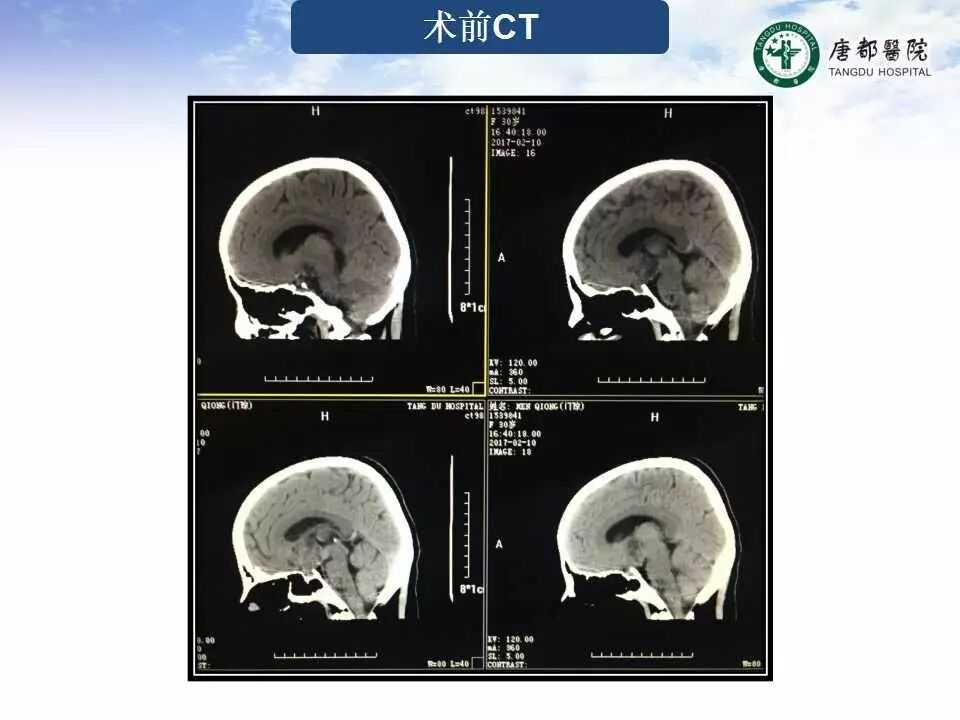

Case 1

长按并识别二维码即可查看该手术视频